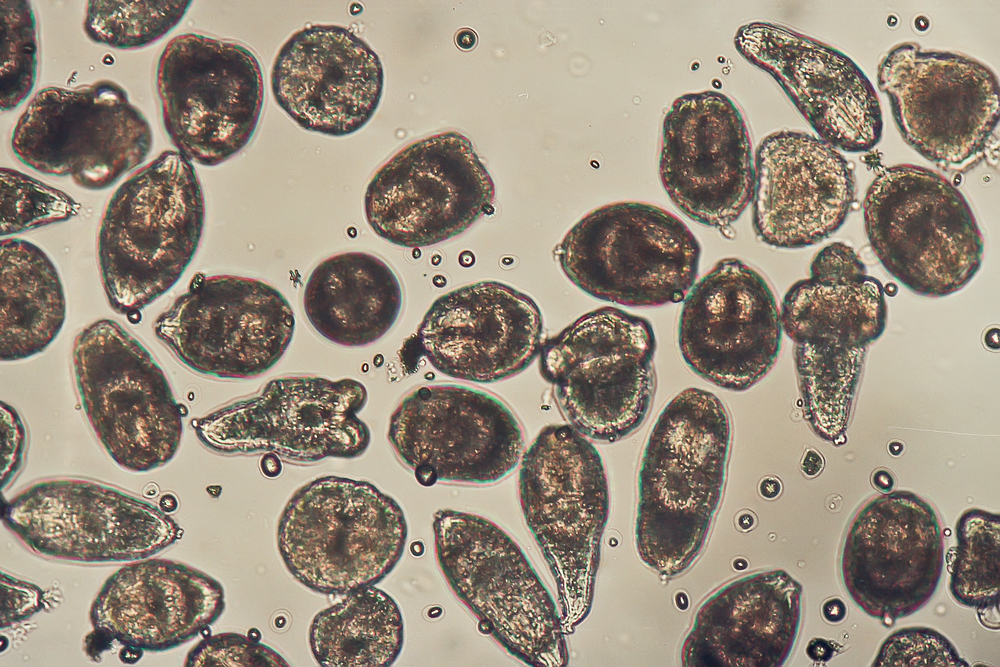

Cells begin to break down

In the first stage, called autolysis, carbon dioxide accumulates in the cells. This creates an acidic environment where enzymes begin breaking down the cells from within.

Bacteria take over in the body

After autolysis, bacteria that were previously kept under control by the immune system begin breaking down the body’s tissues.